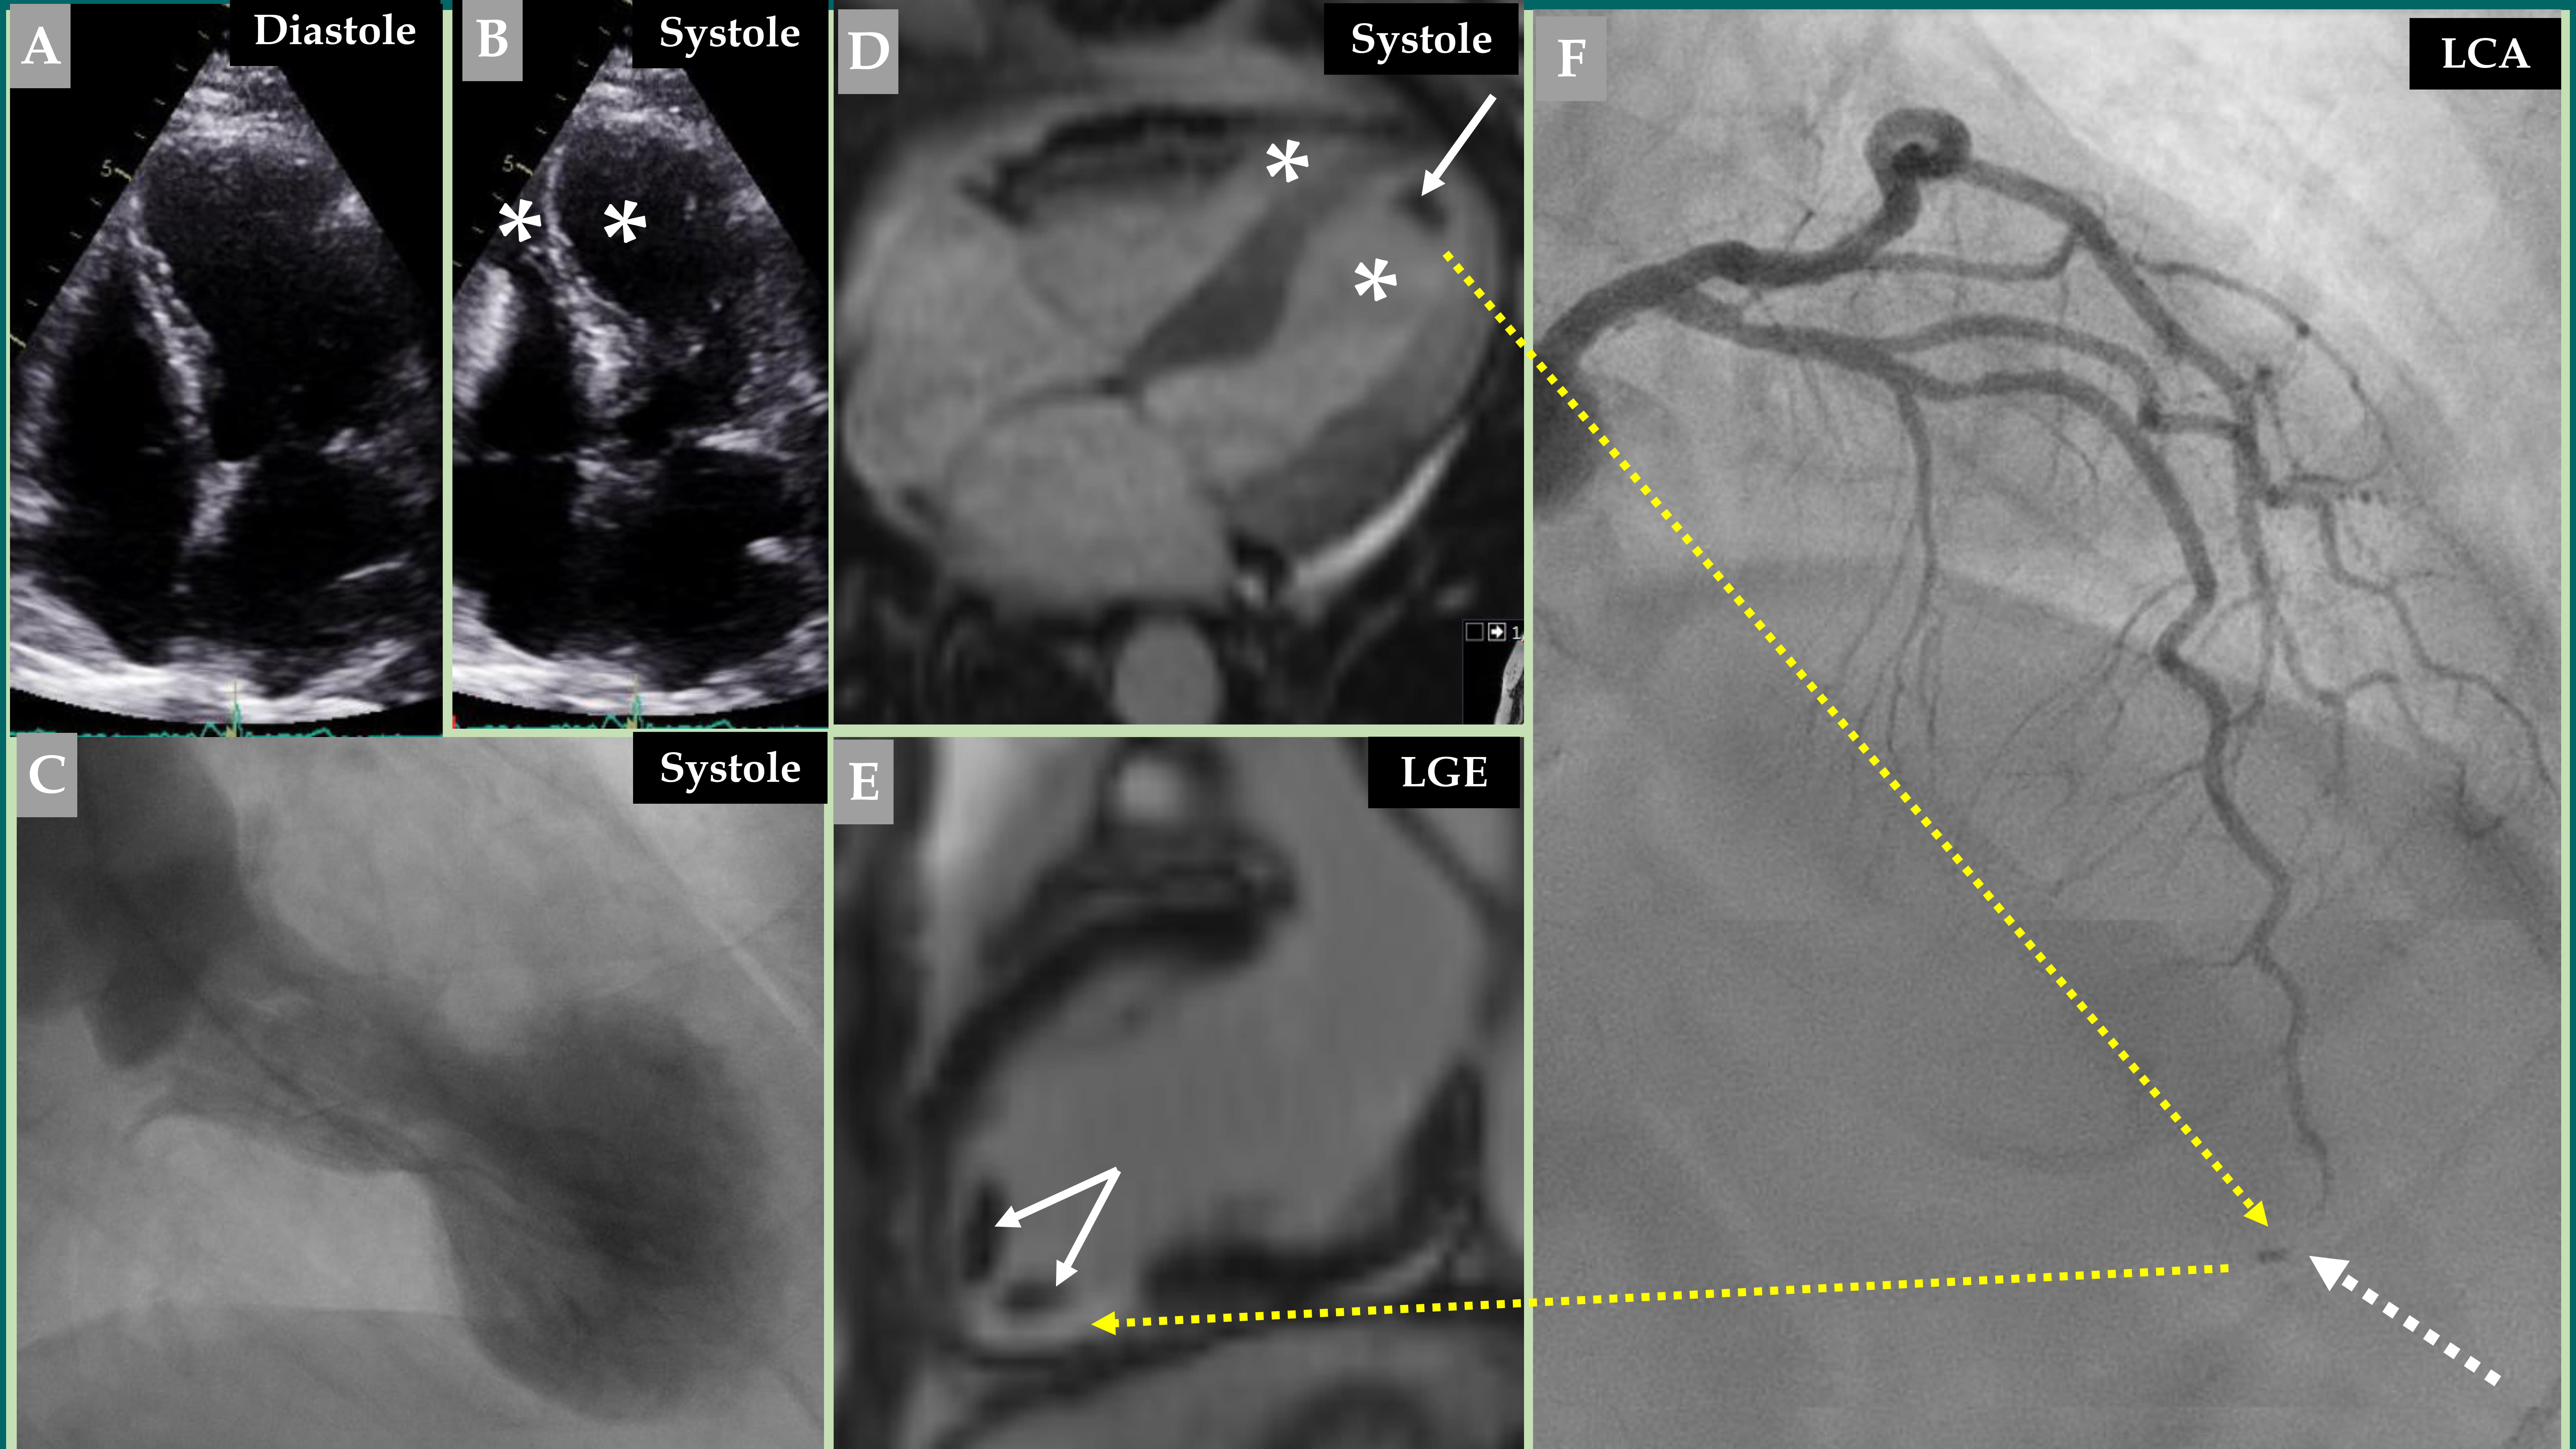

The most common reported sites of cardioembolic complications are cerebral, renal, and peripheral limb arteries [16, 20, 21, 23, 27]. Embolization to the coronary arteries has also been reported [16, 28, 29]. Notably, TS and coronary occlusion may coexist in some cases, which causes difficulties in determining whether the coronary occlusion is the trigger or the consequence. Y-Hassan et al. [16] reported on a 67-year-old woman with a mid-apical pattern of TS triggered by an intense emotional stress. This case was complicated by left ventricular thrombus with an embolic complication to the apical segment of LAD, causing a limited myocardial infarction in the corresponding segment. The small apical LAD occlusion could not explain the extensive LVWMA observed in the mid-apical region caused by TS. That case was also complicated by middle cerebral artery embolization [16]. Fig. 1 presents an illustrative case of a biventricular mid-apical pattern of TS that is complicated by left ventricular thrombi, which have resulted in the LAD embolization at the apical segment, causing acute MI at the corresponding left ventricular region.

Fig. 1. Demonstration of a coronary thromboembolic complication in a patient with a biventricular mid-apical pattern of Takotsubo syndrome (TS). Echocardiography (A, diastole and B, systole) image of a biventricular mid-apical pattern of TS (B, white asterisk in both left and right ventricles). Contrast left ventriculography (C) of the typical mid-apical ballooning pattern of TS during systole. Cine view of cardiac magnetic resonance (CMR) imaging (D) during systole also reveals a biventricular pattern of TS (white asterisk in both left and right ventricles). This was complicated by left ventricular thrombus (white arrow). Late gadolinium enhancement (LGE) view of the CMR imaging (E) shows two thrombi at the apical region of the left ventricle (two white arrows). This view also shows LGE at the apical-inferior region (broken yellow arrow) corresponding to the occluded apical segment of the left anterior descending artery (LAD) (F, broken white arrow). Contrast left coronary artery (LCA) angiography in the right cranial anterior oblique projection shows atheromatous changes with occlusion of the apical segment of LAD (F, broken white arrow) caused by embolization from the left ventricular thrombus (F, broken yellow arrow).